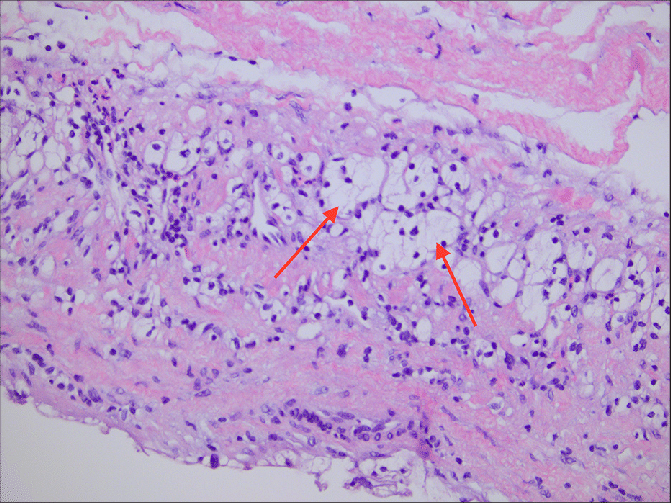

Multilocular cystic renal neoplasm of low malignant potential

Recognized sub-type of clear cell RCC. The cyst lining and fibrovascular sepeta are composed of clear cells with small dark nuclei.

Has an extremely indolent pattern of behavior.